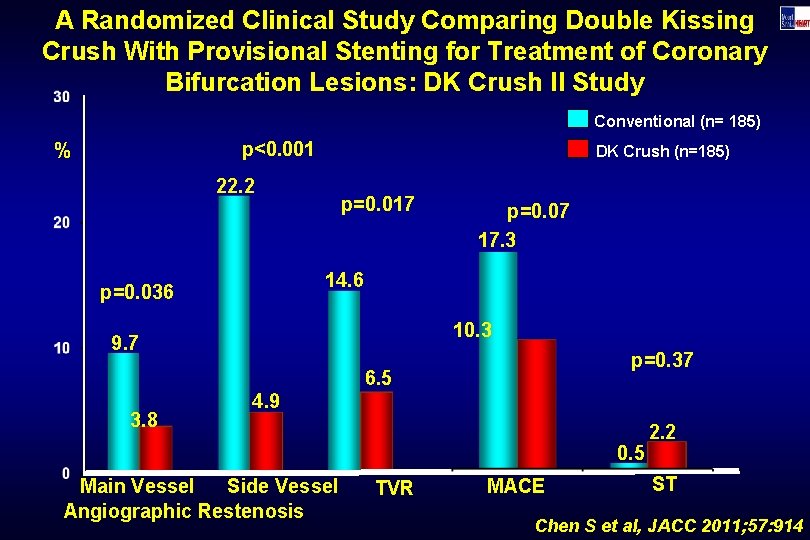

A Randomized Clinical Study Comparing Double Kissing Crush With Provisional Stenting for Treatment of Coronary Bifurcation Lesions: DK Crush II Study Conventional (n= 185) p<0. 001 % DK Crush (n=185) 22. 2 p=0. 017 p=0. 07 17. 3 14. 6 p=0. 036 10. 3 9. 7 p=0. 37 6. 5 3. 8 4. 9 0. 5 Main Vessel Side Vessel Angiographic Restenosis TVR MACE 2. 2 ST Chen S et al, JACC 2011; 57: 914